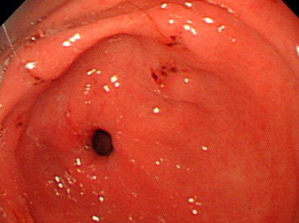

顽固性胃溃疡――无痛胃镜检查

检查过程:做胃镜前只需在患者手臂上注射一只快速入眠针剂,2分钟后患者进入睡眠状态,无痛苦和不适感,一般5分钟即可完成检查。

检查效果:准确诊断各种胃部疾病。

适合人群:慢性胃炎、胃溃疡、反酸、腹痛、烧心、呕吐等胃病患者,年纪较大者不建议采用。

宜宾肛泰肛肠医院胃肠中心针对顽固性胃溃疡,开展无痛内镜下修补治疗,取得了很好的治疗效果。无痛内镜下修补治疗消化道溃疡,特点是把经活检确认不是癌变的溃疡面保护起来,同时再次活检,已再次验证上次活检结果,是目前治疗顽固性胃溃疡较好的治疗方法。